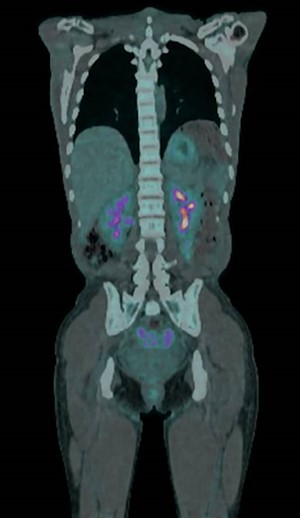

On examination, she had tense ascites but no clinical signs of peritonism. Initial blood tests demonstrated normal inflammatory markers, liver function and electrolytes. A computed tomography (CT) scan of the abdomen demonstrated gross ascites, but no defined pathology, including no mass lesions, portal vein thrombosis or peritoneal changes (Fig. 1). An ascitic drain was inserted and drained 4.6 litres of clear fluid. This was sent for cytology, biochemistry and culture (including for tuberculosis), with the results indicated in Table 1. Tumour markers (CEA, CA125, CA19-9 and AFP) were all within normal limits.

A positron emission tomography-CT (PET-CT) scan demonstrated abnormal tracer uptake in the omentum, right lower abdomen quadrant and pouch of Douglas (Fig. 2). A subsequent diagnostic laparoscopy for targeted biopsies however yielded only inflammatory changes with no signs of malignant processes. Post-operatively, the ascites resolved spontaneously, and on out-patient review at 4 weeks repeat blood tests and all clinical parameters had returned to normal.